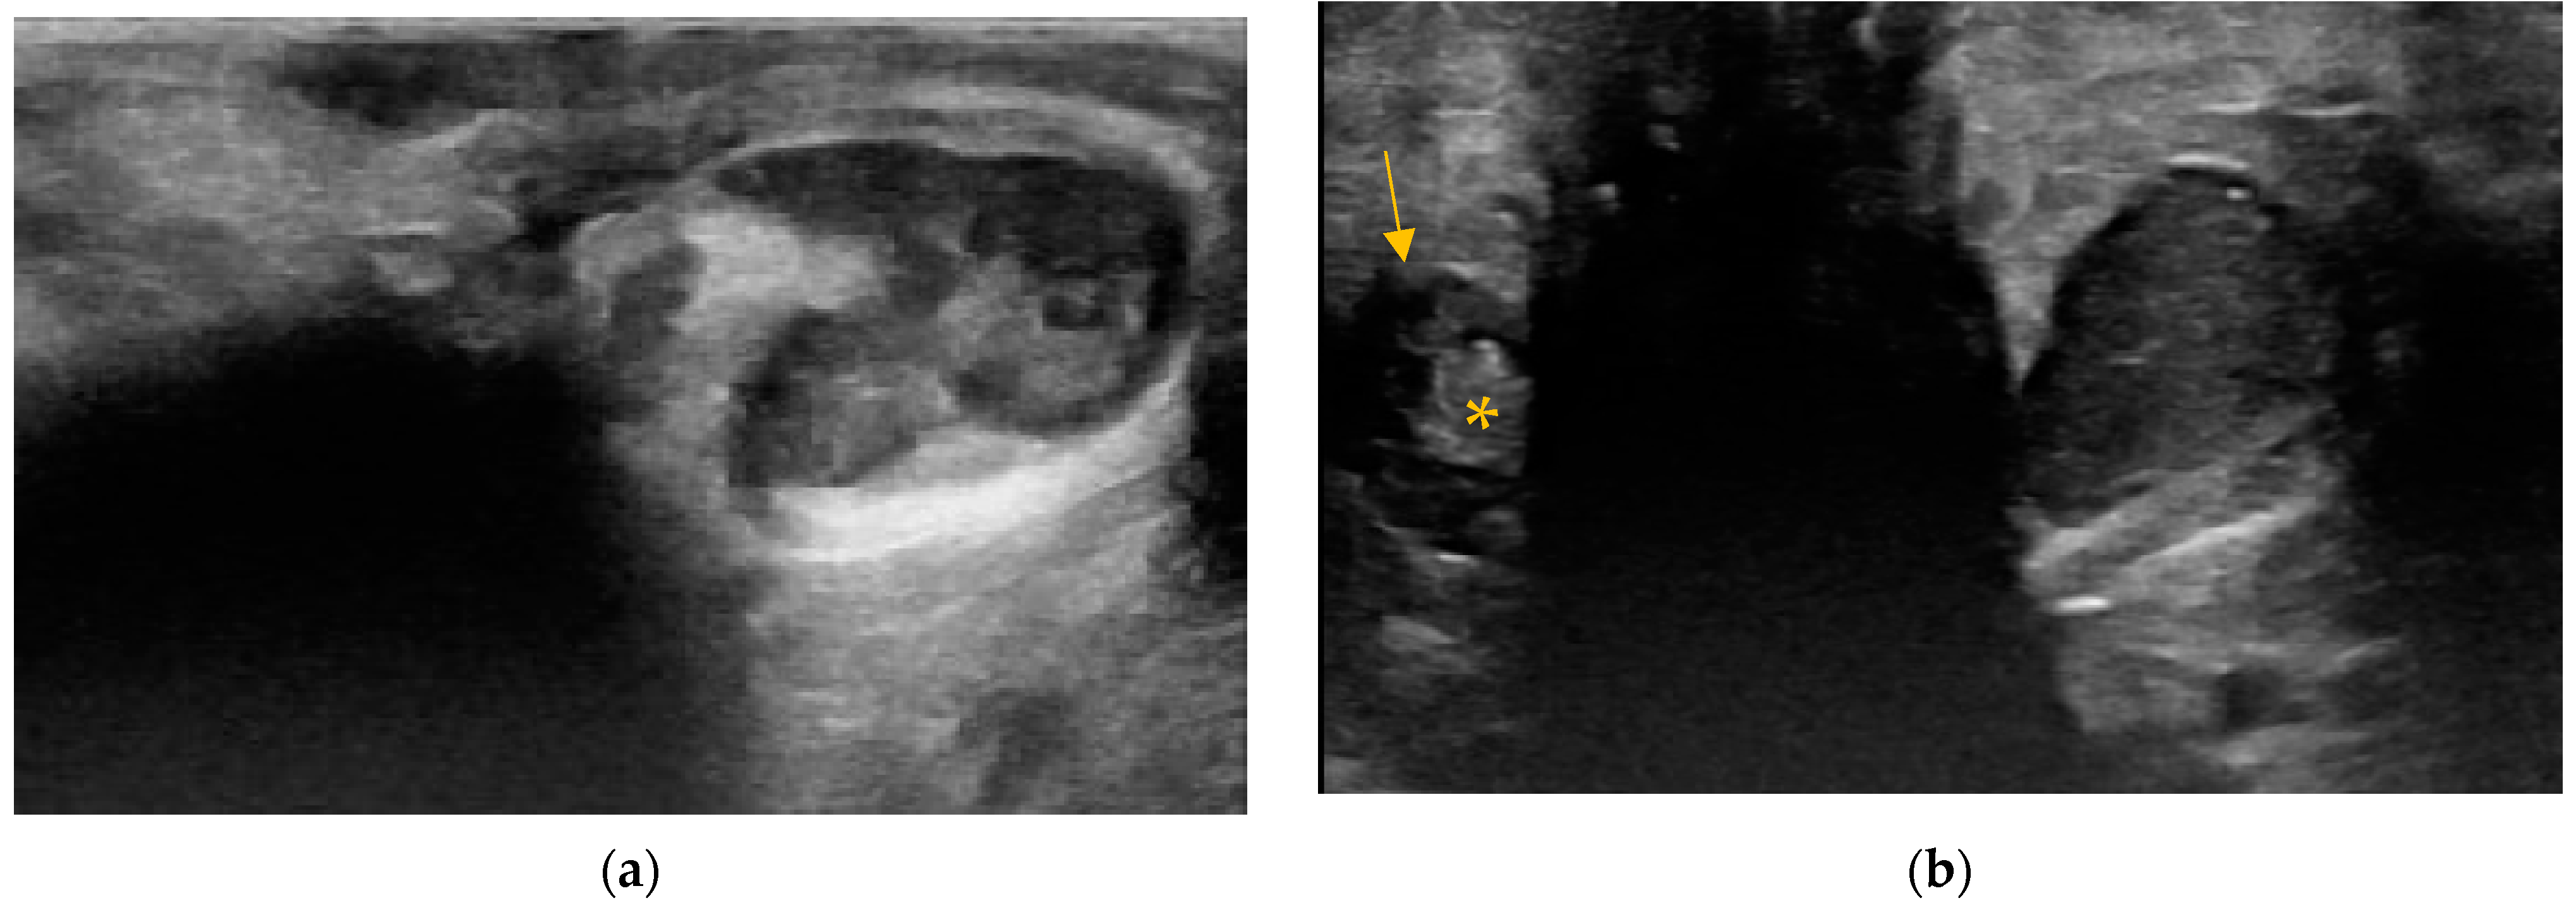

3.2. Content of Anal Sacs

3.3. Size and Shape of Anal Sacs

3.4. Wall of Anal Sacs

3.5. Adverse Findings

4. Discussion